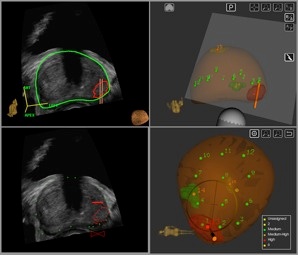

The Scionti Prostate Center has utilized ARTEMIS technology to perform over 3,000 MRI-to-ultrasound precision fusion guided biopsies. We believe that a smart targeted biopsy more precisely identifies the size, location and stage of a prostate cancer.

This figure illustrates the MRI-to-ultrasound fusion process. Ultrasound images on the left of the diagram are fused or superimposed on a model of the prostate made from MRI images. Biopsies can be directed to the MRI abnormalities.